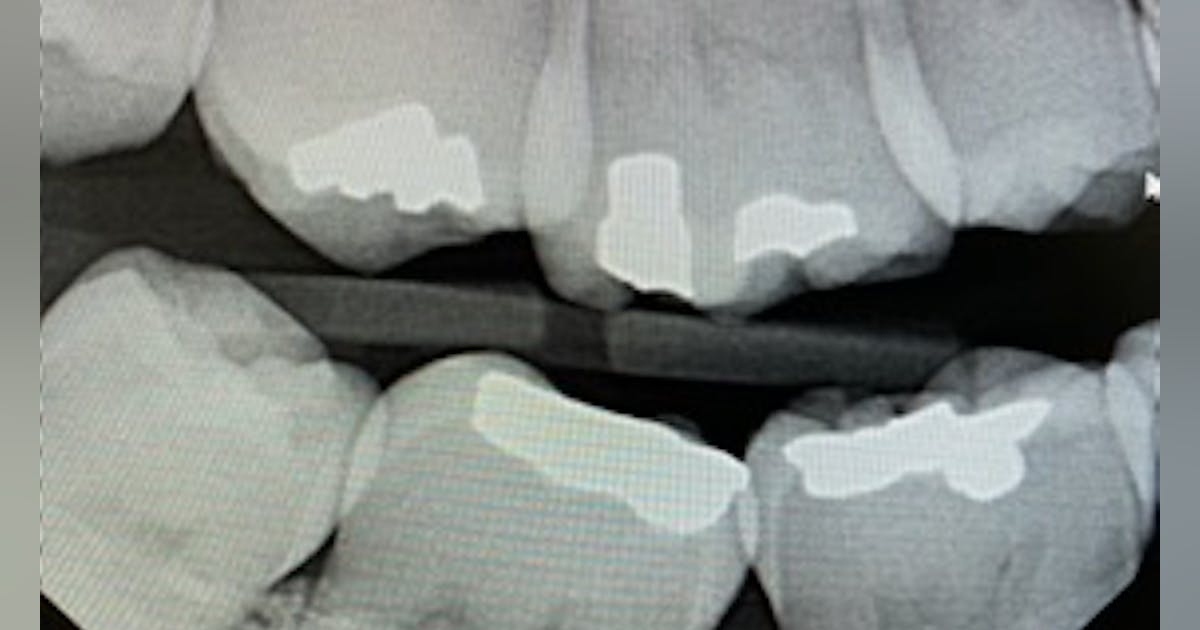

Is this a diagnostic BW?

What is "NO"?

What are the 3 factors we are looking for when taking a diagnostic BW?

What is DOB?

-Direct vision

-Open contacts

-Bone level